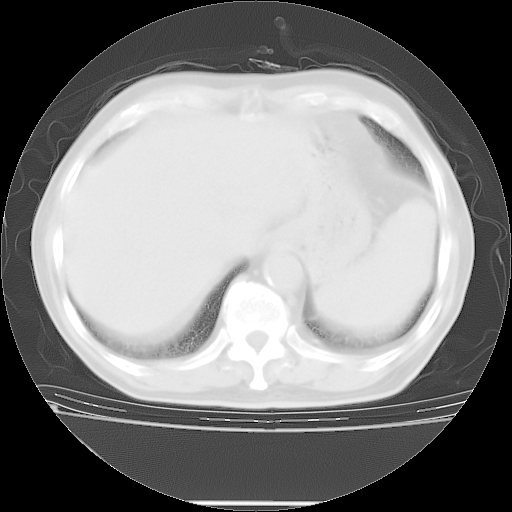

今天复查肺部CT,发现双肺广泛磨玻璃样改变。所以我把3月19日和5月9日相隔50天的肺部CT上传。请大家会诊。

2009年3月19日肺部CT片。

5月9日肺部CT(在4月27日齐鲁医院肺部CT描述部分肺组织磨玻璃样改变,12天后肺组织广泛磨玻璃样改变)